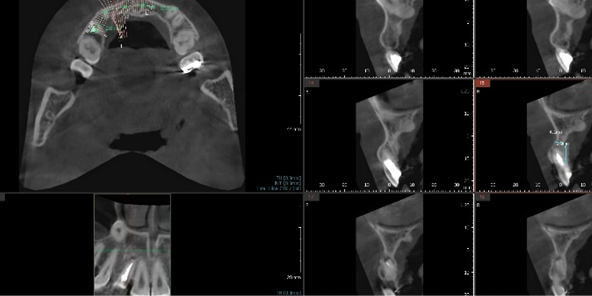

3D 모의 수술로 최적 식립 위치 계산

3차원 CT사진과 구강스캐너를 이용하여

미리 가상의 수술을 거쳐서 수술 위치를 정하고

수술 후 상부 위치까지 예측해서

미리 보철물을 만들어 두었다가

당일 수술 후 보철물을 붙이는

네비게이션 임플란트 방식입니다.